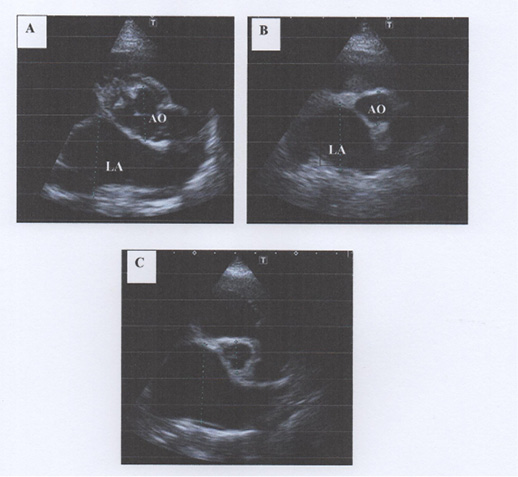

Dilation of left atrium (LA) on right parasternal short axis left atrium/aorta (AO) view. A: Mild dilation of left atrium with LA to Aorta ratio of 1.56, B: Moderate dilation of the left atrium with LA:Ao of 2.04 and C: Severe dilation of left atrium with LA:Ao of 2.47. Note that the normal LA:Ao ratio should be <1.3 (Reproduced from Rishniw et al., 2000)